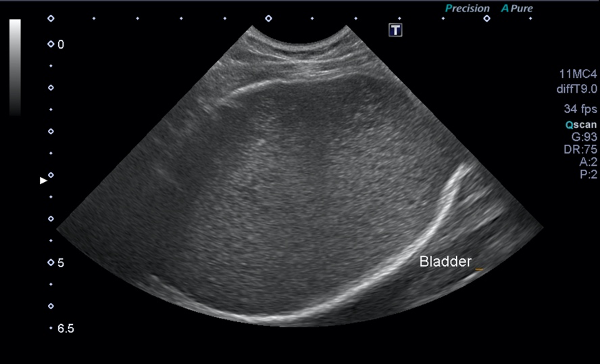

超音波検査で膀胱内に多量の尿が認められ、膀胱内の尿はモザイク様に観察されました。

尿検査では重度の血尿が認められました。